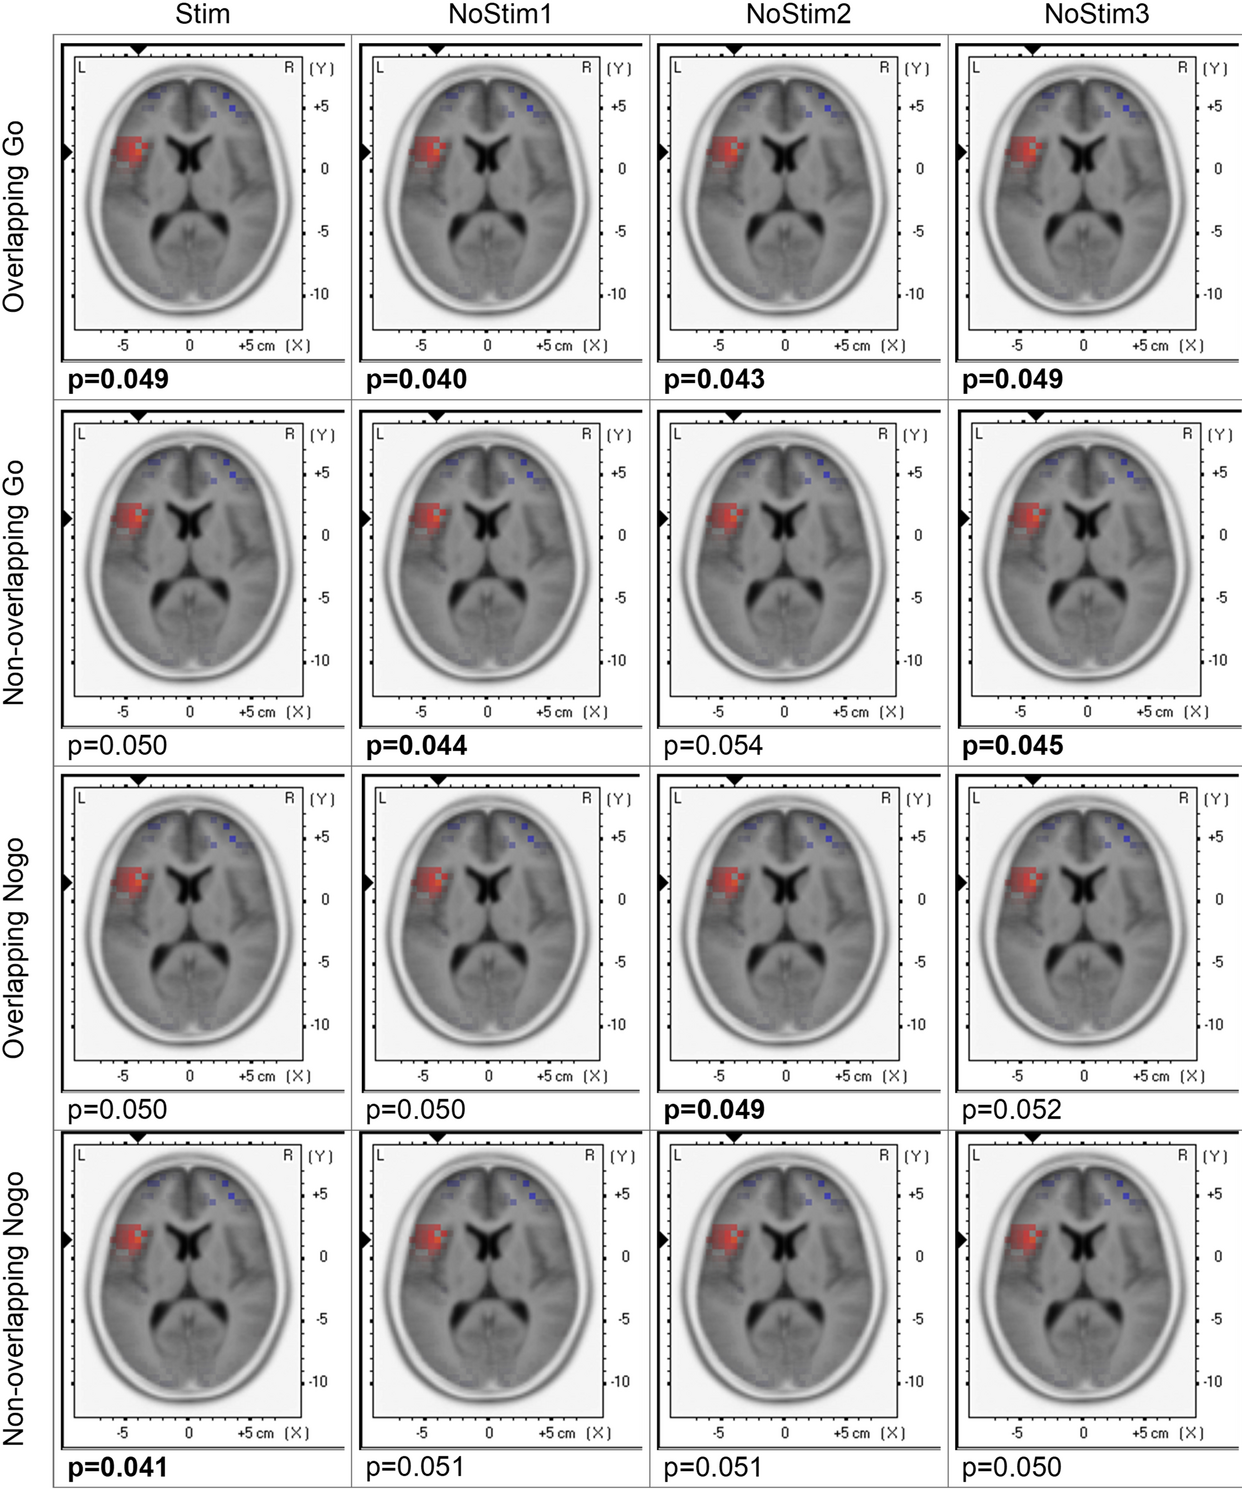

Fig. 5

From: Modulation of response inhibition with event-related atVNS showed EEG but no behavioral effects

Visualization of the activity of brain regions after stimulation. sLORETA plots contrasting the effects of verum and sham stimulation within 500ms to 700ms after stimulus presentation for all trial types, such as overlapping/non-overlapping Go and Nogo trials, for both verum and sham stimulation, separately for stimulated (Stim) and non-stimulated trials (Nostim1/NoStim2/NoStim3). Significant p-values are indicated in bold. All plots demonstrate modulations in left Brodmann area 13, Insula, and sub-lobar area.